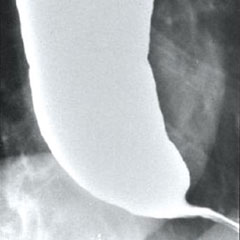

식도와 위의 경계 부위인 하부식도 괄약근이 좁아져 있는 식도조영술 사진. / 순천향대병원 제공

이 병은 발견이 쉽지 않다. 내시경으로도 잘 안 보여 역류성 식도염으로 오진하는 경우가 많다. 또, 상당수 환자는 흉통을 의식해 심장내과를 전전한다. 가장 확실한 검사법은 식도의 압력을 보는 식도내압검사와 식도의 모양을 보는 식도조영술이다. 치료는 내시경으로 이완이 안되는 근육에 보톡스 주사를 놓거나, 풍선을 넣어 식도를 넓히는 풍선확장술로 한다.